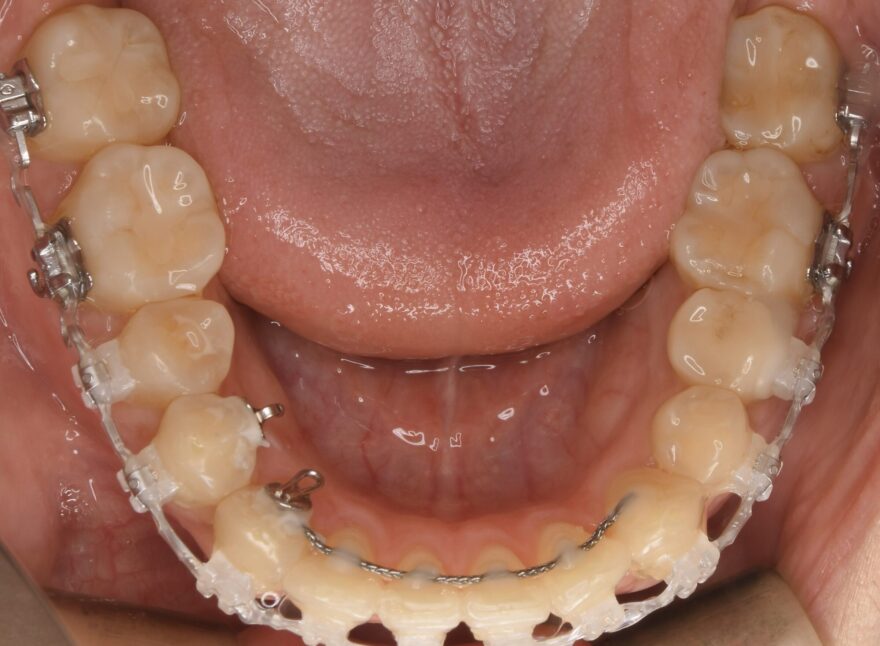

治療中の口腔内写真

上顎は裏側に矯正装置が付いています。